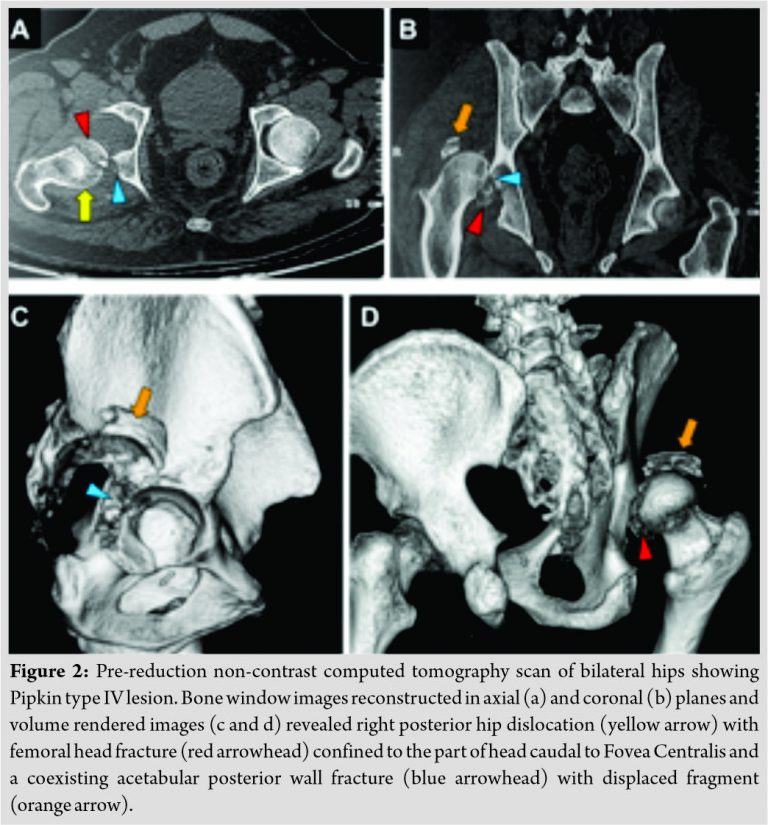

Pre-reduction non-contrast computed tomography scan was performed for further evaluation. Images were reconstructed in bone window and volume rendered images were also obtained. The study confirmed the findings of radiography and revealed right posterior hip dislocation with femoral head fracture confined to the part of head caudal to Fovea Centralis. There was a coexisting isolated acetabular posterior wall fracture. Hence, the lesion was classified as Pipkin type IV (Fig. 2).